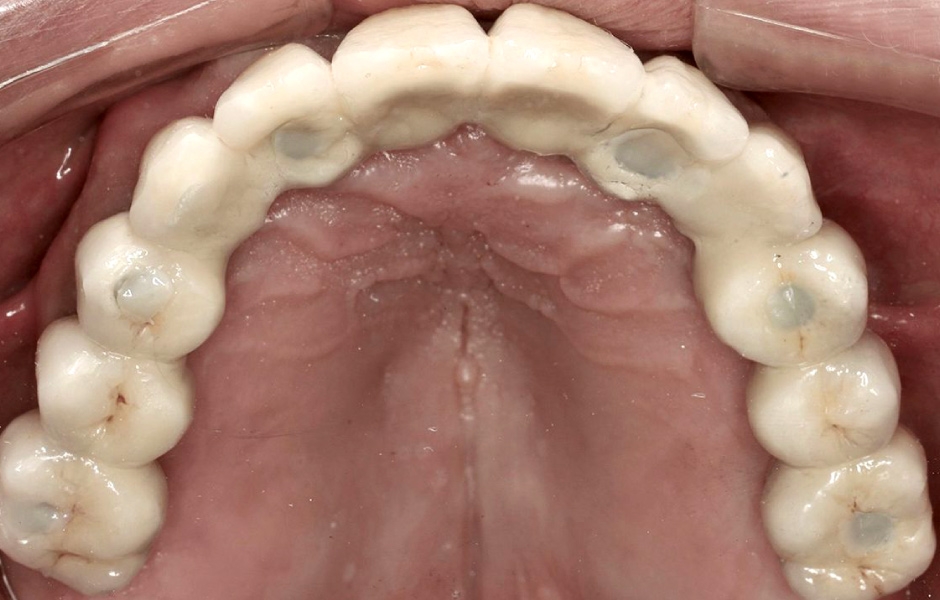

K dokončení protetického ošetření jsme využili skenovací pomůcku Straumann® RevEX™ Scanbody pro plně monolitický návrh náhrady s kompletně digitálním výrobním postupem. Nejprve byl proveden intraorální sken protilehlého oblouku, následovaný intraorálním skenem ošetřovaného oblouku s přišroubovanými dočasnými abutmenty. Poté byl proveden sken skusu a intraorální sken měkkých tkání s nasazenými šroubovanými abutmenty pro definitivní náhradu. Na provizorní náhradu byly připevněny reverzní skenovací pomůcky Straumann® RevEX™ Scanbody a náhrada byla nasnímána extraorálně. Následně byl navržen a vyfrézován prototyp náhrady a také verifikační šablona. (obr. 45, 46).

Při další návštěvě byly vyfrézovaný prototyp náhrady a verifikační šablona vyzkoušeny v ústech a následně byl dokončen návrh a výroba definitivní náhrady (obr. 47, 48).

Obr. 45

Obr. 46

Obr. 47

Obr. 48